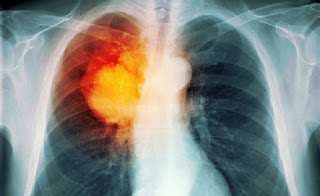

For some ladies, bosom disease may appear like a capital punishment. Around 1 in 8 American ladies will create bosom growth in their lifetime however a clinical trial may have figured out how to free us of it for the last time later on.

The late Cancer Research UK-subsidized trial found that it is conceivable to treat bosom tumor without expecting to experience chemotherapy. Strikingly, because of a mixed drink of two bosom malignancy drugs known as Herceptin (Trastuzumab) and Tyverb (Lapatinib), 11 percent of the tumors were found to have completely vanished inside only two weeks. A further 17 percent of cases highlighted drastically contracted tumors after a basic change in treatment.

The two medications are regularly utilized as a part of bosom malignancy treatment as of now, yet this is the first occasion when they had been consolidated together and utilized before surgery and chemotherapy. Scientists planned to utilize these medications to battle a protein called HER2 (human epidermal development element receptor 2) which influences the development and division of malignancy cells.

Some carcinogenic bosom cells have a high number of HER2 receptors and they are called HER2 positive bosom tumors. It's assessed that 15-25% of female bosom malignancy patients experience the ill effects of a HER2 positive disease. HER2-positive bosom diseases are forceful and can require broad treatment to cure. In addition, these diseases will probably return.

257 ladies with HER2 positive bosom tumor were chosen for the study, with half being put on the medication combo and the other half were the control bunch. What they found was that of those on the medication, 11% had no growth cells staying inside two weeks and 17% of cases included significantly contracted tumors.

The control bunch, which got just Herceptin, saw none of the members malignancy free and just 3% encountering a lessening in tumor size. Unmistakably, the blend Herceptin and Tyverb was effective.

Shockingly, Herceptin's authorizing just permits it to be accessible in conjunction with chemotherapy. Ideally, the aftereffects of this study can change that.